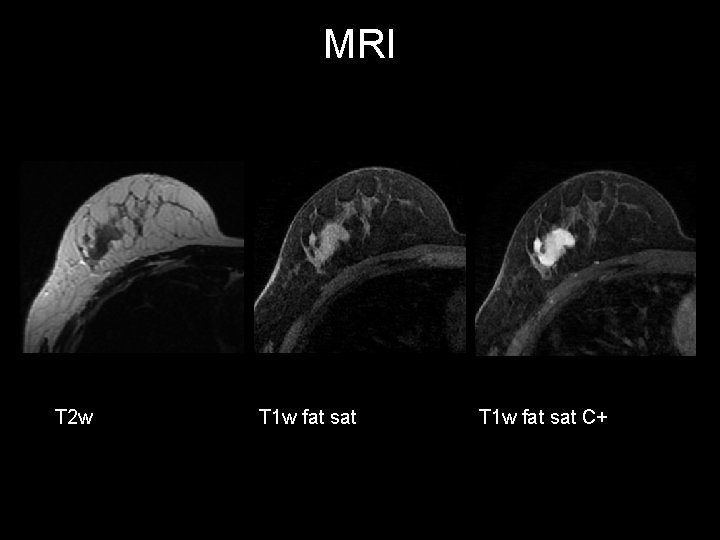

Annual screening T 2 w T 1 w fat sat C+

Annual screening INVASIVE LOBULAR BREAST CANCER http: //radiopaedia. org/cases/invasive-lobular-breast-cancer